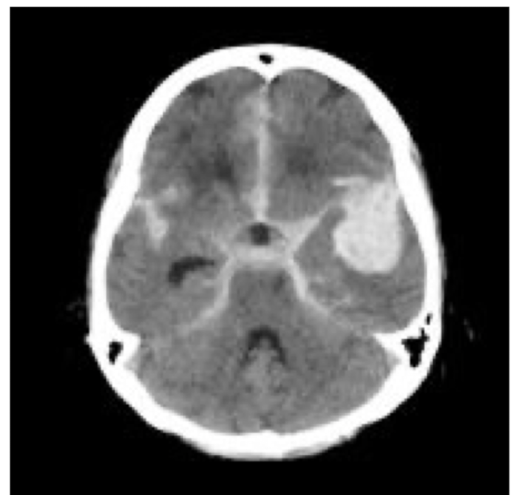

CT protocol + Pathology?

• Brain C-

• Subarachnoid haemorrhage: brain bleed within the subarachnoid space and pia mater

• Hyper attenuation within the basal cistern

• Located around the circle of Willis